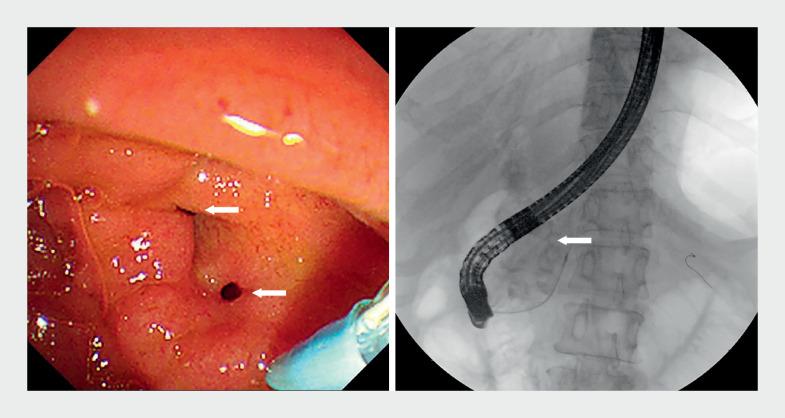

Multiple pancreaticobiliary fistulas combined with acute necrotizing pancreatitis: a rare complication of pancreatic extracorporeal shock wave lithotripsy.

摘要